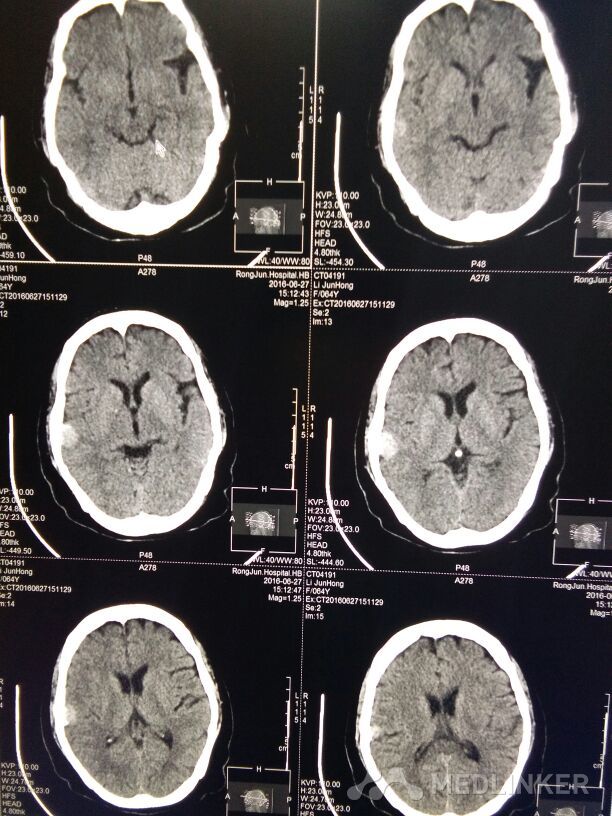

右颞叶脑膜瘤

所见:右颞叶可见一卵圆形稍高密度影,大小约1.2x1.9cm,边缘可见钙化,周围无明显水肿,余脑实质密度正常,脑室系统及脑沟,裂未见明显异常中线结构居中。 提示:右颞叶脑膜瘤。